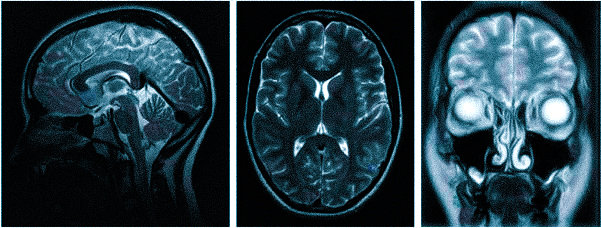

МРТ при головных болях (в трех проекциях) позволяет получить объемные изображения, что помогает выявить даже незначительные изменения и отличить патологию от нормы.

- МРТ (магнитно-резонансная томография) — процедура, которая предоставляет полное представление о состоянии исследуемой области и позволяет выявить заболевания. Четкие снимки получаются благодаря воздействию магнитного поля на организм.

МР-томография позволяет диагностировать опухоли головного мозга, нарушения мозгового кровообращения, сосудистые поражения (например, аневризмы) и последствия различных заболеваний, включая инсульт. Обследование помогает выявить серьезные болезни, которые могут проявляться хроническими или периодическими головными болями.